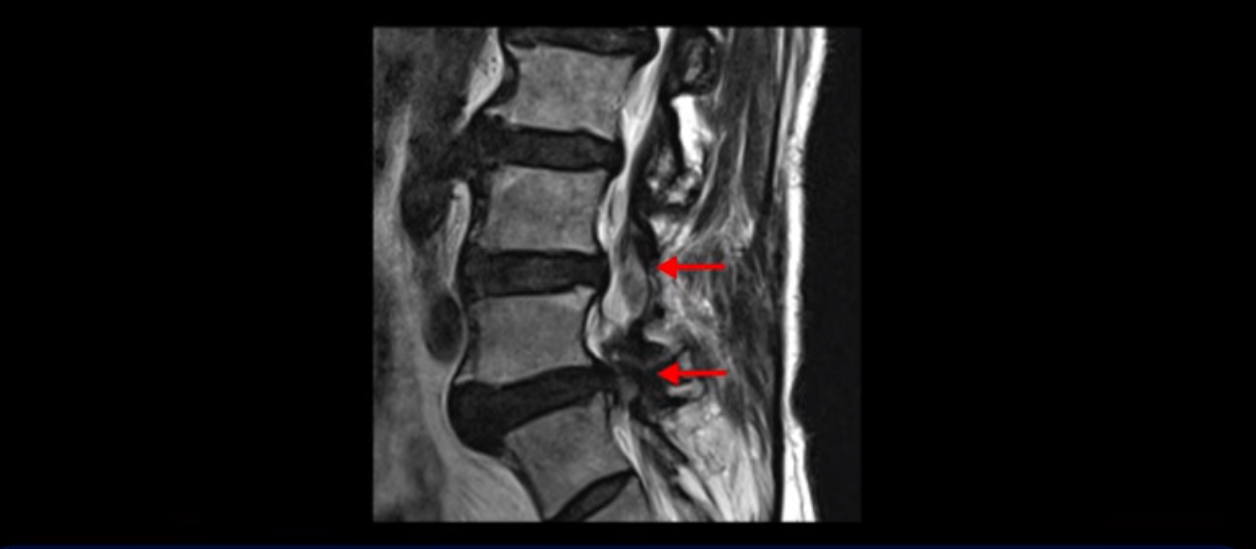

이 환자분은 협착증 수술을 두 번 받은 뒤에 또 다시 다리 방사통이 심해지고 발목 마비 증상(풋드랍)이 생겨서 이번에는 유합술을 권유받은 환자분입니다. 먼저 MRI를 보고 설명해 드린 후 이런 환자분의 방사통과 발목의 마비와 힘 빠짐이 어떻게 수술 없이도 좋아질 수 있는지 그리고 치료는 어떻게 하는지 자세히 설명드리겠습니다.

이분은 허리 다섯 마디 중 4번 5번, 5번 1번에 감압술로 눌린 신경을 풀어주는 수술을 받았습니다.

후관절을 떼어낸 흔적이 보입니다.

하지만 중심성 협착은 여전히 심한 상태입니다.

이분은 오른쪽, 왼쪽 다리에 모두 방사통이 심하고 왼쪽 다리에 마비 증상, 즉 풋드랍(족하수) 증상이 있습니다. 왼쪽 신경 가지가 빠져나가는 추간공을 보면 두 마디가 좁아져 있습니다.

이런 신경 구멍이 좁아져 있는 걸 협착이라고 합니다.

이미 앞선 두 번의 수술로 뼈와 인대 등을 일부 제거해서 안정성이 떨어진 상태에서 추가로 수술하려니까 척추가 너무 불안정해져 무너질 게 걱정되니까 이번에는 나사 박는 유합술을 권유 받은 겁니다. 이런 환자분들의 방사통과 마비 증상이 어떻게 수술 없이 좋아질 수 있을까요? 치료는 어떻게 하는 걸까요?